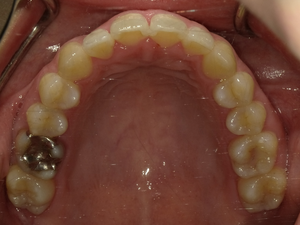

●ご相談内容:歯がガタガタしてる●矯正の種類:マウスピース型矯正「インビザライン」●治療期間:26週間●治療費用:66万円(税込)